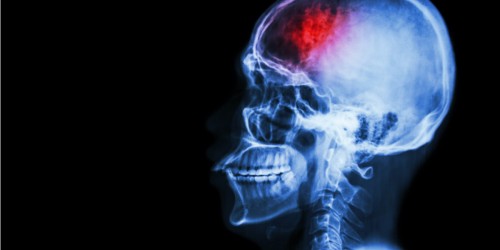

Hello! Does anyone can tell me one thing? I don’t know what is the best source for following problem. I want to know can brain stroke happen when someone suffers from endocarditis? It would be nice to know something about this. I am not educated person in this field and really I need little help. I want to thanks for any response.

Hi! As I see you need information. I will try to answer to your question with my experience. You want to know can brain stroke happen when someone suffers from endocarditis? The Infective endocarditis may be a cause for a brain stroke. Bacteria or fungi that cause endocarditis create a heap. That heap may be relocated. This is the case that is called emboli.